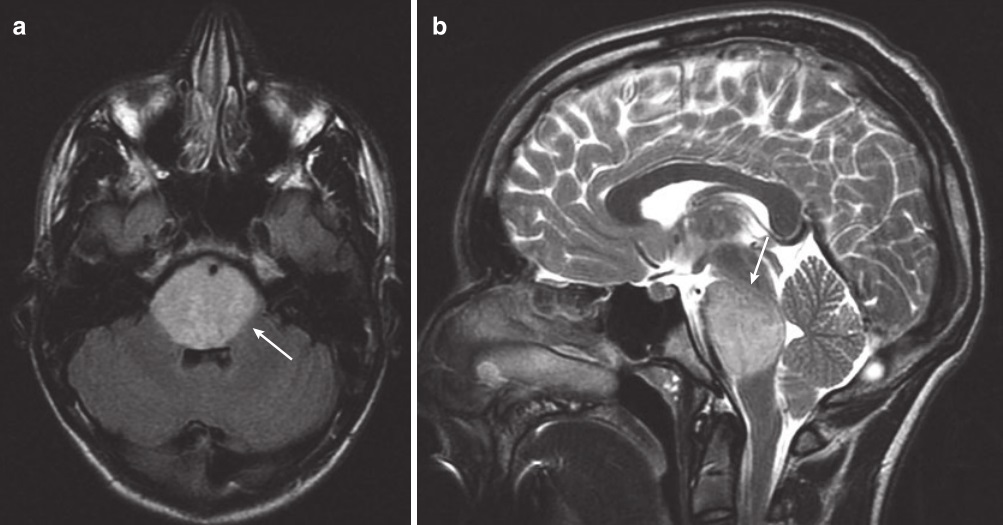

图3:一名14岁男孩的MRI扫描,他有短暂的复视、共济失调和左侧面瘫。(a)轴向FLAIR MRI显示高信号占据整个脑桥(箭头)。(b)矢状T2 MRI显示DIPG使脑桥范围受累(箭头)

3.诊断方法:DIPG的诊断常常通过MRI进行。通常,脑桥弥性扩大,占脑干该区域的50-75%或更多。可能有外生成分,是腹侧。增强后可能会有强化,但通常是斑片状的,合并脑桥弥漫性肿胀。有时,基底动脉可能完全被肿瘤覆盖(图3)。其他MR序列和技术已用于DIPG,包括显示较低的平均总胆碱浓度的磁共振波谱成像(MRS)和弥散张量成像(DTI),但这些在评估病变的神经病理学特点以及结局方面并未被证明是可靠的。